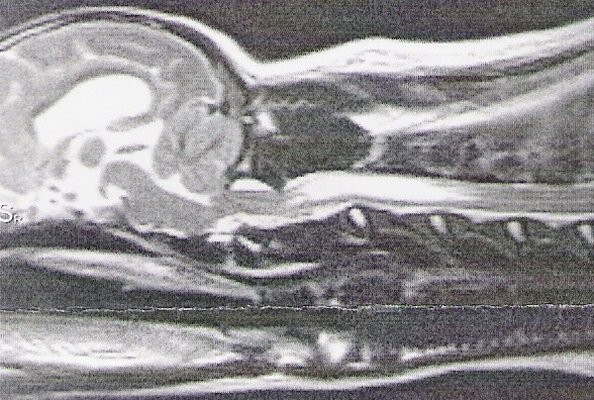

Based on my findings, a study was eventually done to determine

if a skull x-ray could be used to determine amount of CM. The

more CM, the more likely there is to be SM--in most cases. This

study did show there was one skull measurement that did indicate

amount of CM. Here is a comparison of two skull x-rays which

show why this particular measurement indicates amount of CM. The

top one is a skull x-ray of a Cavalier with severe CM (and has

SM as well) and the bottom one is a skull x-ray of a Cavalier

with very little to no CM (and no SM).

The line was drawn from right in front of the 'hole'

(black spot), center of that curved bone (the 'jaw hinge' area)

to where the most thickened area of the skull ends (and the

occipital area begins). In the dog with almost no CM and no SM

you can CLEARLY see there is a lot more lower backskull left

behind/below that line as compared to the dog above--which

literally has almost none! This also happens to be the area

where the cerebellum sits so it would be common sense that the

dog in the top x-ray would have much less room for the

cerebellum than the dog on the bottom--and therefore more CM (chiari

malformation). There just isn't any skull left for there to be

enough room for the cerebellum. It appears here that a good

skull x-ray may be very useful in determining amount of CM and

therefore breeding towards a goal of less and less CM in future

offspring and thereby lessening the prevalence of SM. A skull

x-ray is much cheaper than an MRI which will enable many more

breeders to x-ray for amount of CM in the future as more

information becomes available.